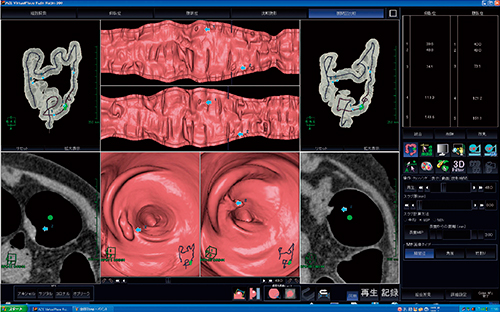

図1 2体位比較読影のレイアウト:比較読影画面

観察方向,位置が同期されており,読影が容易である。